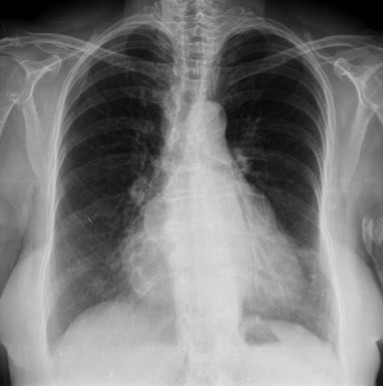

Solución: Es un estudio Normal. Silueta cardiomediastínica y parénquimas pulmonares sin alteraciones significativas.

En esta sección nos dedicaremos a la radiografía simple del Tórax. Iremos introduciendo casos de manera periódica con diversa semiología, así el objetivo es día a día quedarnos con un concepto radiológico fundamental, que luego nos sea de ayuda en nuestra práctica clínica rutinaria.

- Comprobar que la placa está bien centrada e inspirada (6 arcos costales anteriores ó 9 posteriores).

- Abdomen y Diafragma

- Partes blandas y estructura ósea.

- Mediastino con silueta cardiaca.

- Parénquimas pulmonares (por separado)

- Comparar un pulmón con otro.

Seguir esta sistemática, dejando el pulmón para el final no nos olvidaremos de lo más importante.

Regla: Acaso Tiene Mucha Patología Pulmonar (Abdomen, Tejidos blandos y hueso, Mediastino, Pulmón por separado, Pulmón bilateral)

Nota: ¡¡¡No olvidar la placa lateral!!! La regla a seguir es la misma. Leer abdomen y diafragma, examinar parte posterior, tejidos blandos y subir por la columna; tráquea y descender por mediastino. Finalmente pulmones.